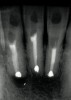

Figure 22   Radiograph with initial penetration of surgical length  friction grip conical carbide bur. A slight redirection of the bur is indicated.

Figure 22

Figure 23   Radiograph of deeper endo-exploration with the latch grip version of the conical carbide bur. Position confirmed as accurate.

Figure 23

Figure 24   Shortly afterward Figure 23 radiograph was taken, the ideal angle of intersection of the residual pulp nicely directs the file into the calcified pulp chamber

Figure 24